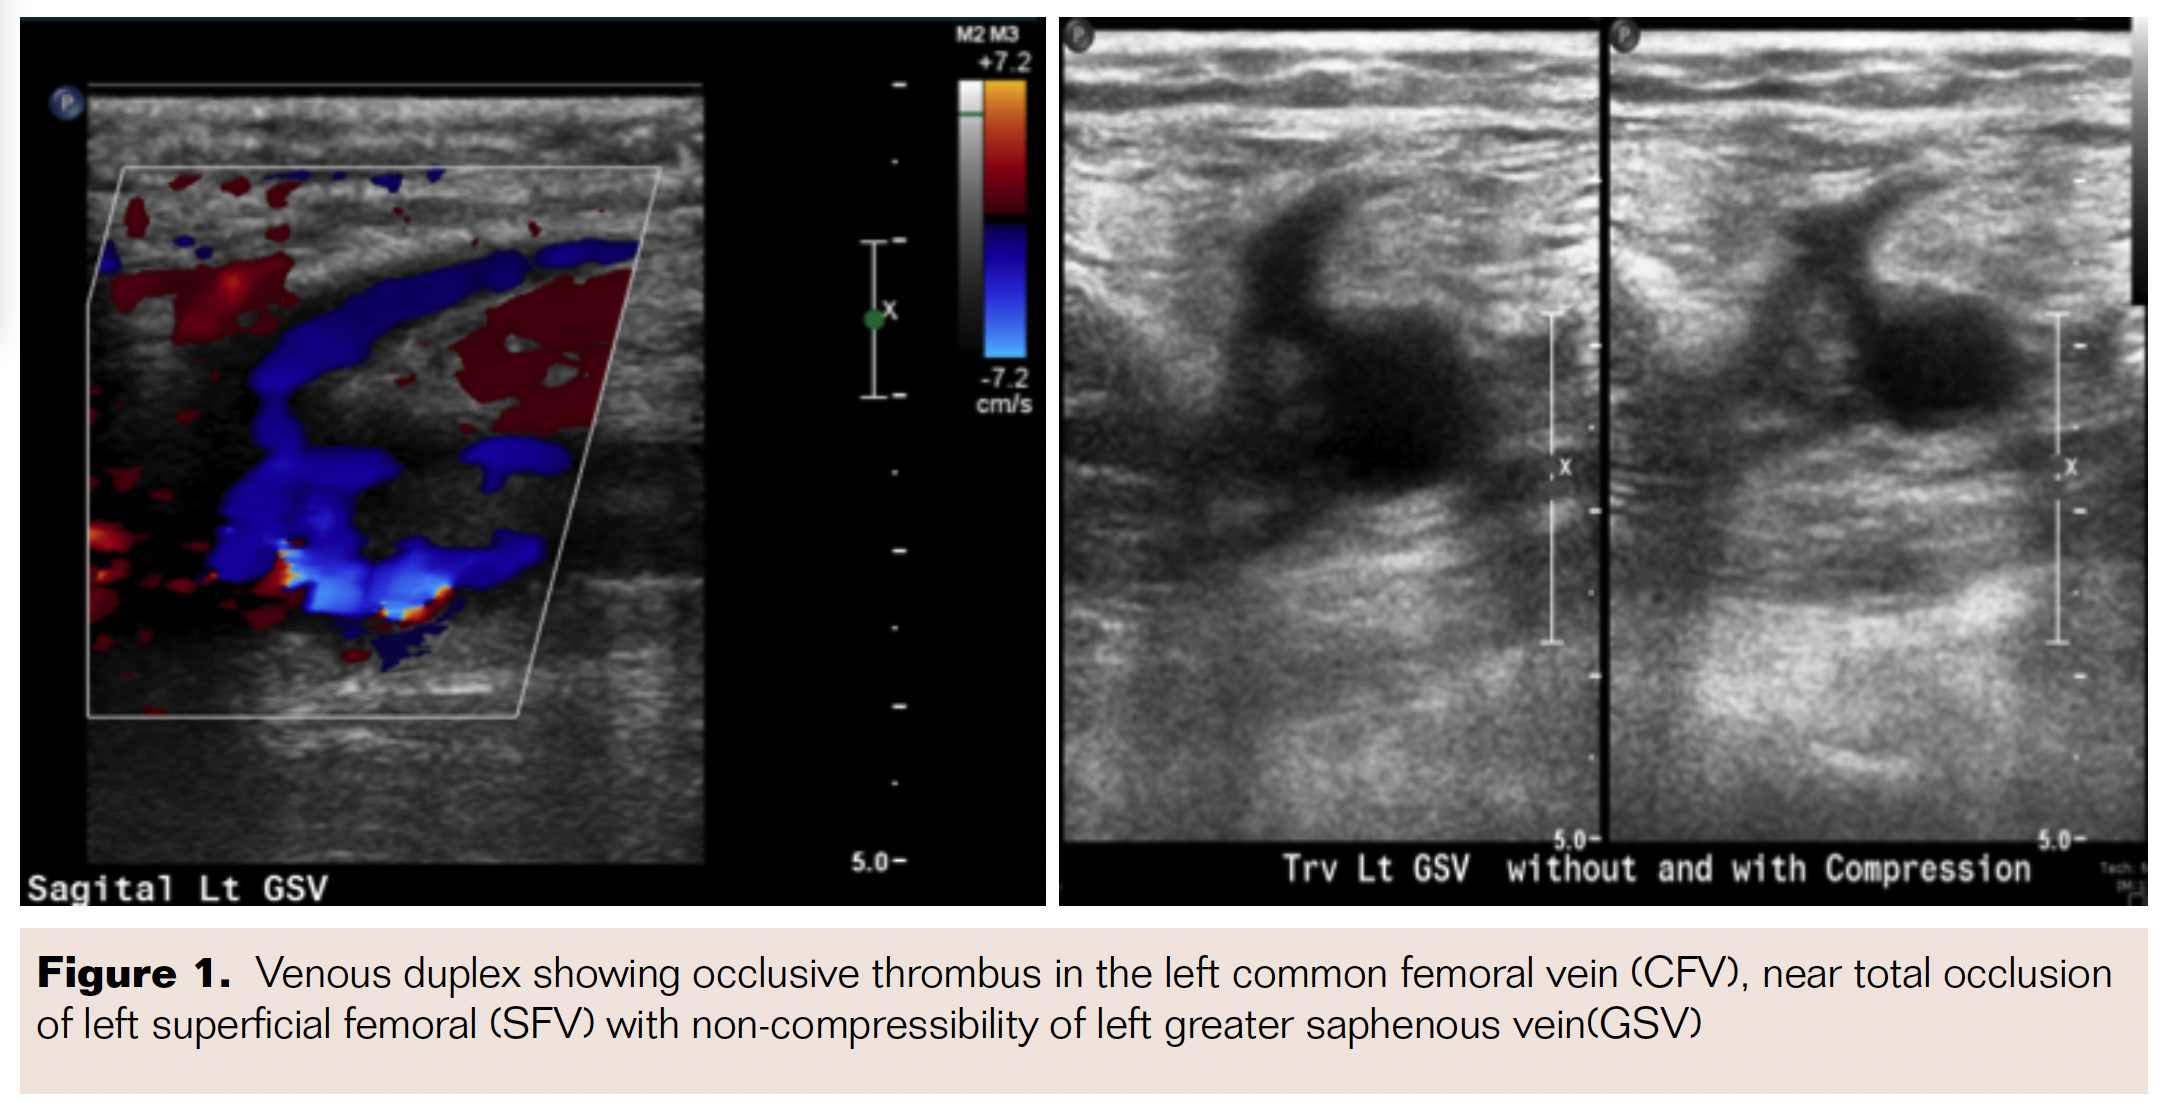

Selective left lower-extremity venography was performed with the patient placed in supine frog-legged position and ultrasound-guided 6 Fr sheath placement in left popliteal vein using micropuncture access kit. Selective venogram confirmed left popliteal scarring with 50%-60% stenosis, with 100% occlusion of the femoral vein with collateral branches filling the distal CFV above the femoral head (Figure 2). A TriForce coaxial crossing system (Cook Medical) was then advanced over a stiff Glidewire to cross the occlusion in the femoral vein to enter the reconstituted segment in the CFV. Intravascular ultrasound confirmed severe compression of the left common iliac vein (CIV) up to 60.4% area compression (Figure 3). A 24 x 45 mm self-expanding Wallstent (Boston Scientific) was deployed in the left CIV and postdilated using a 16 x 40 mm Mustang XXL balloon (Boston Scientific) with good expansion (Figure 4). Following this, 14 x 80 mm, 10 x 80 mm, and 8 x 150 mm self-expanding Protégé stents (Medtronic) were deployed in the left CFV, proximal to mid femoral vein, and mid to distal femoral vein, respectively. The CFV was postdilated using a 12 x 40 mm Mustang balloon and the remainder of the stented segment was postdilated using a 6 x 200 mm EverCross balloon (Medtronic) with good expansion. Final venogram revealed excellent angiographic result with brisk flow through the entire stented segment (Figure 5), with excellent stent apposition under intravascular ultrasound imaging.